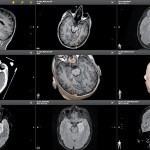

Ablauf der Visualase-Laserablation

Die Visualase-Therapie ist ein innovatives Verfahren, das mithilfe eines präzisen Lasersystems von Medtronic erkranktes Gewebe im Gehirn gezielt behandelt. Durch einen minimal-invasiven Eingriff wird eine winzige Laserfaser in das Gehirn eingeführt, um das betroffene Gewebe zu erhitzen und zu zerstören. Die Behandlung erfolgt unter Echtzeit-MRT-Bildführung, wodurch eine hohe Präzision und Sicherheit gewährleistet werden.

Im Zuge der Vorbereitung der Visualase-Laserablation werden kernspintomographische Aufnahmen des Gehirns des Patienten oder der Patientin angefertigt, computergestützt bearbeitet und am virtuellen 3D-Modell der Eingriff geplant. Anhand dieser Darstellung legen Epilepsie-Spezialist Prof. Dr. Christian Elger und der erfahrene Neurochirurg und Operateur Prof. Dr. med. Thomas Gasser im stereotaktischen Verfahren den genauen Zielpunkt für die Laserablation fest.

Anschließend wird die MR-gestützte Laser-Abtragung mit der hochmodernen OP-Software präzise vorgenommen. Der Eingriff erfolgt unter Vollnarkose. Über einen nur 1,6 mm messenden Zugang wird die Medtronic LASER-Sonde in das Gehirn eingeführt.

- Die Person liegt hierbei im MRT, dessen Bilder in Echtzeit auf die mobile Kontrollstation übertragen werden. Von dort aus beobachten die Experten die Ebenen im Gehirn, durch die der Katheter bis hin zur zu behandelnden Stelle geführt wurde, und überwachen die Thermoablation.